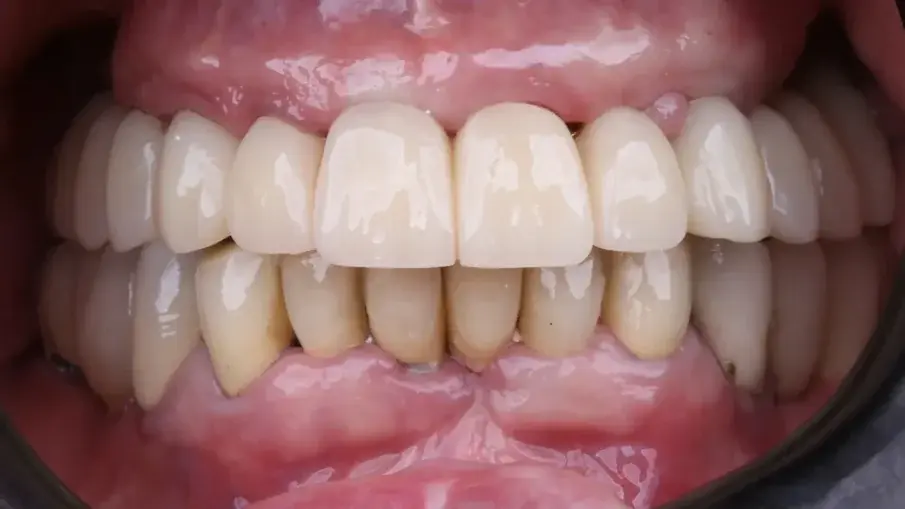

При последната среща беше поставена окончателната хибридна винтово-фиксирана протеза. Окончателната протеза се състоеше от CAD/CAM титанова рамка, завинтена към всички импланти, и три монолитни циркониеви протезни сегмента, залепени отгоре (фиг. 18а–в). Беше оценена оклузията и пациентът беше включен в четиримесечна програма за поддържане. При последната контролна визита (една година след поставянето на имплантите) всички импланти бяха успешни и пациентът беше удовлетворен от новата протеза (фиг. 19–22).

Фиг. 19: Окончателна протеза при едногодишното проследяване, фронтален изглед.